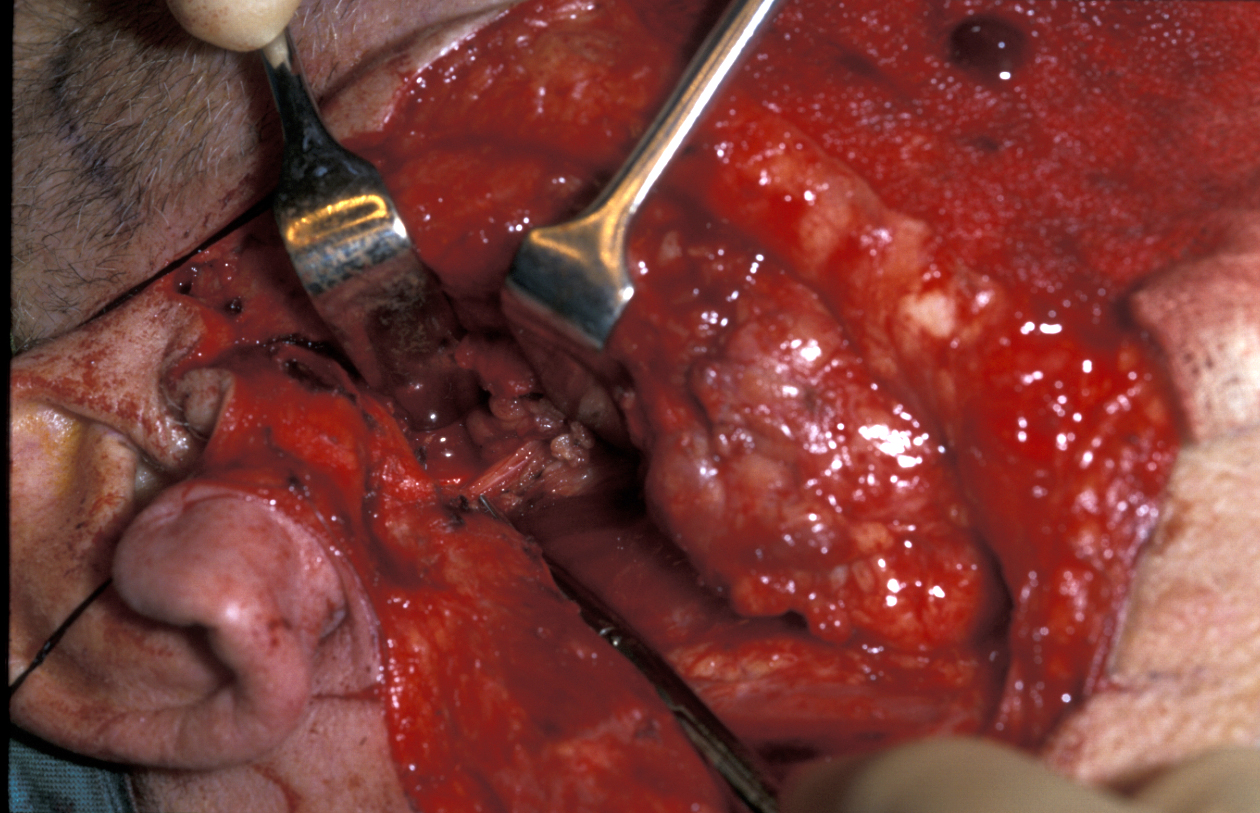

Another location where salivary gland pleomorphic adenoma may occur is in the palate area, most often at the junction of hard and soft palates (see Figure 7).

Figure 7: Palatal pleomorphic adenoma arising at a typical site.

Figure 8: Excision of palatal pleomorphic adenoma by using a cleft palate gag to aid access. Subperiosteal stripping provides an adequate margin and heals well by allowing simple granulation to occur.

For all tumours which overlay the hard palate, simple subperiosteal excision with a mucosal margin is adequate (see Figure 8). Healing by secondary intention (leaving the wound as is) of the palate is excellent and can be achieved by using a dressing plate with a sedative and soothing dressing. If the tumour extends into the soft palate, the capsule of the tumour can be elevated from the underlying levator aponeurosis (a thin structure that connects the levator muscle (the muscle responsible for lifting up the soft palate when saying ‘ahhh’) . The soft palate defect will granulate with good functional result. If the levator aponeurosis is breached, however, this has to be repaired and should be reconstituted with vascularised tissue, such as a buccal fat pad flap, or a temporoparietal fascial flap.